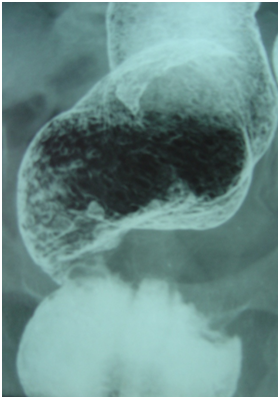

A female of 37years presented with per rectal bleeding for 8years to the Department of Radiology of Tribhuvan University Teaching Hospital in 2007 for a barium enema study. Her elder brother had similar symptoms and he had undergone colectomy. Her late father also suffered from recurrent episodes of per rectal bleeding. Two big brothers died in childhood. Her sister had also died of distension of abdomen. She has two children who are asymptomatic. Her double contrast barium enema study shows multiple round filling defects involving the whole colon including the rectum (Figure 1). Barium study of her brother showed irregular large filling defect in the rectum due to malignant mass in addition to multiple small filling defects (Figure 2).

Figure 2 Barium study of the patients’ brother showed irregular large filling defect in the rectum due to malignant mass in addition to multiple small filling defects.